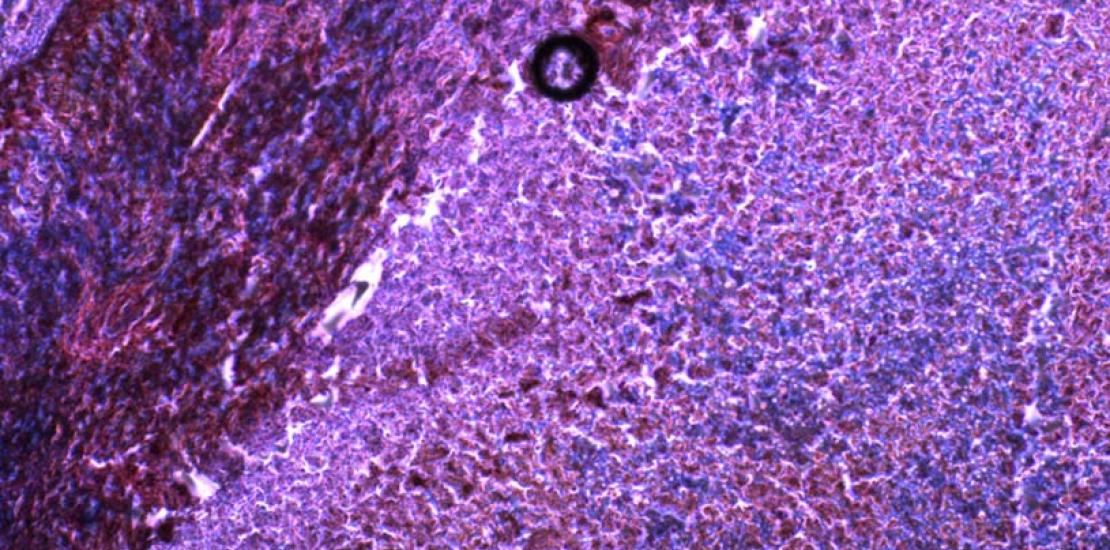

Las regiones de hipoxia en las muestras tumorales se correlacionan con la señalización celular relacionada con la supresión del sistema inmunológico.

Los tumores a menudo crecen tan rápido que no disponen de la sangre suficiente en el tejido, creando un ambiente en el que falta oxígeno (hipoxia). En estas condiciones, las células cancerosas comienzan a autodestruirse, salvo en algunos tipos de cáncer, en los que se ha visto que el microambiente privado de oxígeno que rodea al tumor lo protege frente al sistema inmune.

Esta hipótesis fue confirmada mediante nuevos experimentos. Usando modelos de ratón y muestras de tejido humano, los investigadores encontraron que un ambiente de hipoxia desencadenaba un aumento de los niveles de miR25 y miR93 creando una cascada de señalización celular que finalmente provocó una disminución en los niveles de cGAS. Cuando los investigadores inhibieron miR25 y miR93 en células tumorales, los niveles de cGAS se mantuvieron altos en tumores hipóxicos.